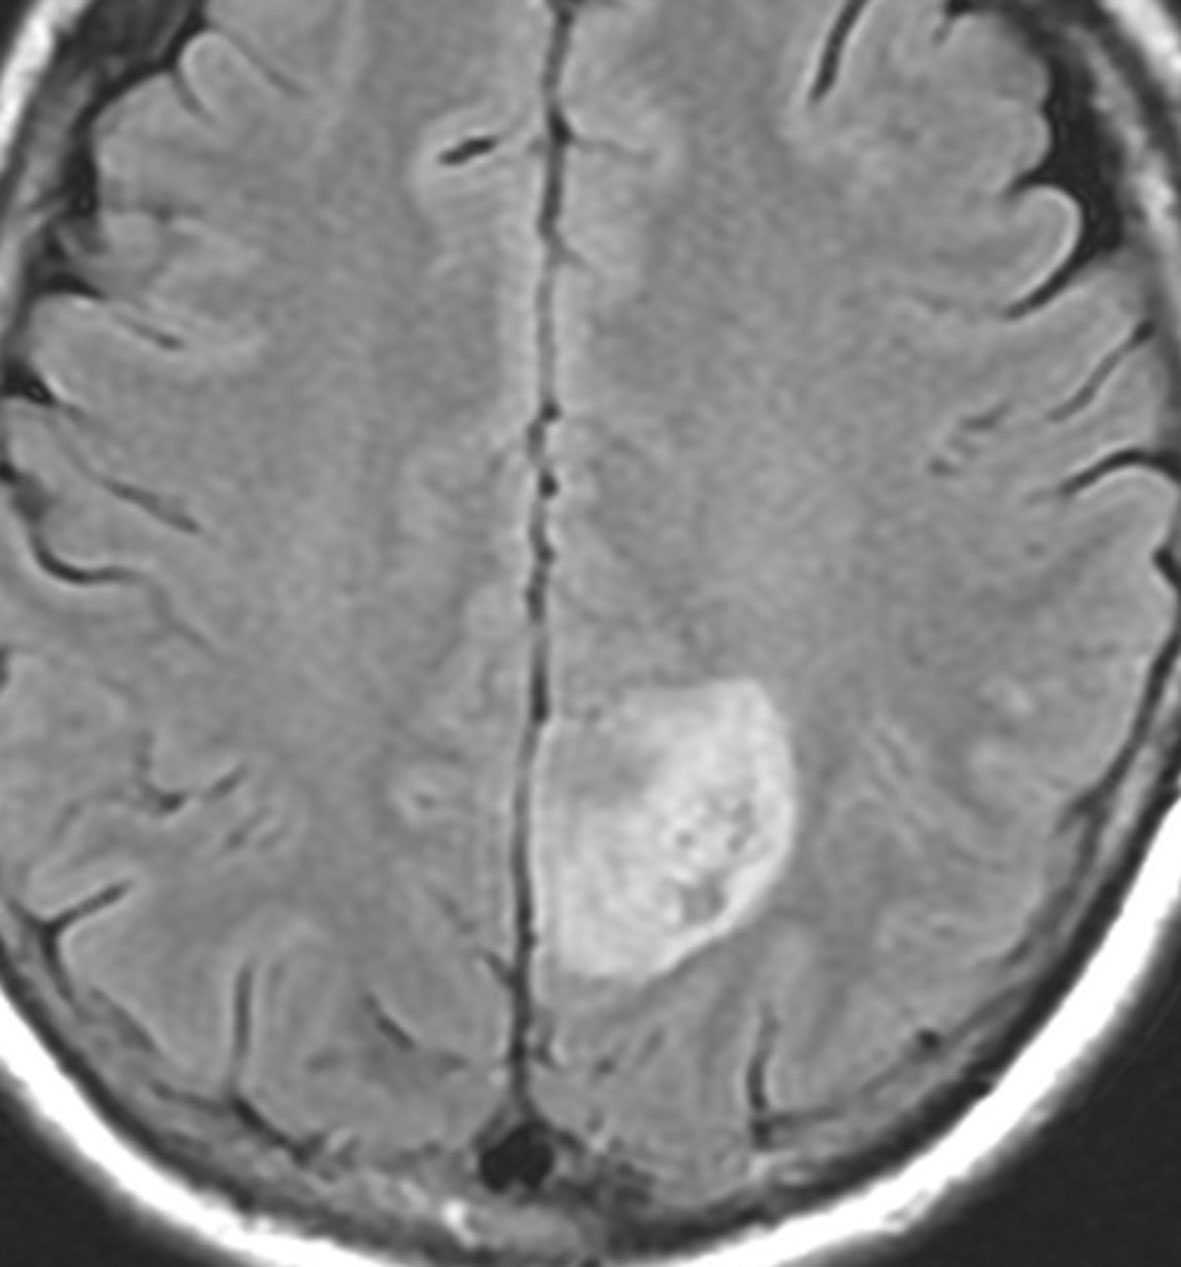

成人の頭頂葉の例

無症状で偶然発見されたものです。CTで石灰化があり,部分的にガドリニウム増強されます。乏突起膠腫グレード2との鑑別が難しい例です。乏突起膠腫より放射線化学療法に治療抵抗性ですから,もちろん治療選択は全摘出です。